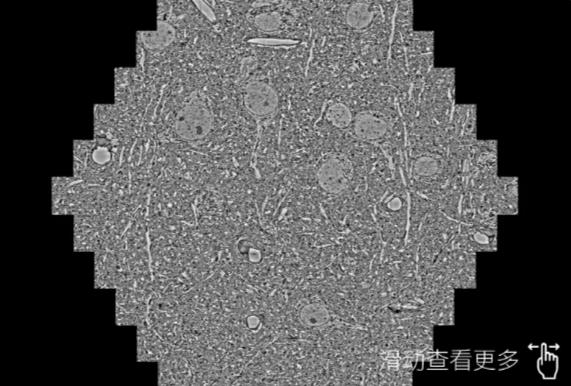

鼠脑切片。左图使用宣城蔡司宣城扫描电镜MultiSEM706对165μmx143pm面积区域成像,耗时仅需1.5秒。右图为鼠脑切片中30μm区域放大效果。样品由芝加哥大学B.Kasthuri提供。

使用蔡司高速宣城扫描电镜MultiSEM对1mm²人脑皮层组织进行高分辨成像,并对其中的各种细胞结构进行三维重构分析。左图展示了2x3mm²组织平面中锥体神经元的三维重构效果。右图显示了局部体积神经元三维重构。图像由哈佛大学chtman实验室提供,渲染图由D. Berger 制作。